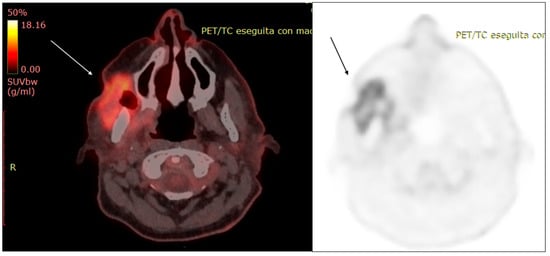

- Fosko, S.W.; Hu, W.; Cook, T.F.; Lowe, V.J. Positron Emission Tomography for Basal Cell Carcinoma of the Head and Neck. Arch. Dermatol. 2003, 139, 1141–1146. [Google Scholar] [CrossRef] [PubMed]

- Kawaguchi, M.; Kato, H.; Matsuyama, K.; Noda, Y.; Hyodo, F.; Matsuo, M. Prognostic value of 18F-FDG PET/CT and MRI features in patients with high-risk and very-high-risk cutaneous squamous cell carcinoma. Br. J. Radiol. 2022, 95, 20211003. [Google Scholar] [CrossRef]

- Mahajan, S.; Barker, C.A.; Mauguen, A.; Singh, B.; Pandit-Taskar, N. Restaging [18F] fludeoxyglucose positron emission tomography/computed tomography scan in recurrent cutaneous squamous cell carcinoma: Diagnostic performance and prognostic significance. J. Am. Acad. Dermatol. 2020, 82, 878–886. [Google Scholar] [CrossRef]

- Mahajan, S.; Barker, C.; Pandit-Taskar, N. FDG PET/CT in staging cutaneous squamous cell carcinoma. J. Nucl. Med. 2017, 58, 121. [Google Scholar]